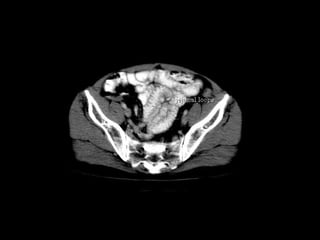

Radiographers use medical imaging equipment like X-rays and MRIs to produce images of patients' internal structures and organs. They are responsible for positioning patients, operating scanning machines, and ensuring quality images. Radiographers must have strong attention to detail, excellent communication skills, and the ability to work well under pressure to accurately capture anatomical features and diagnose any abnormalities.